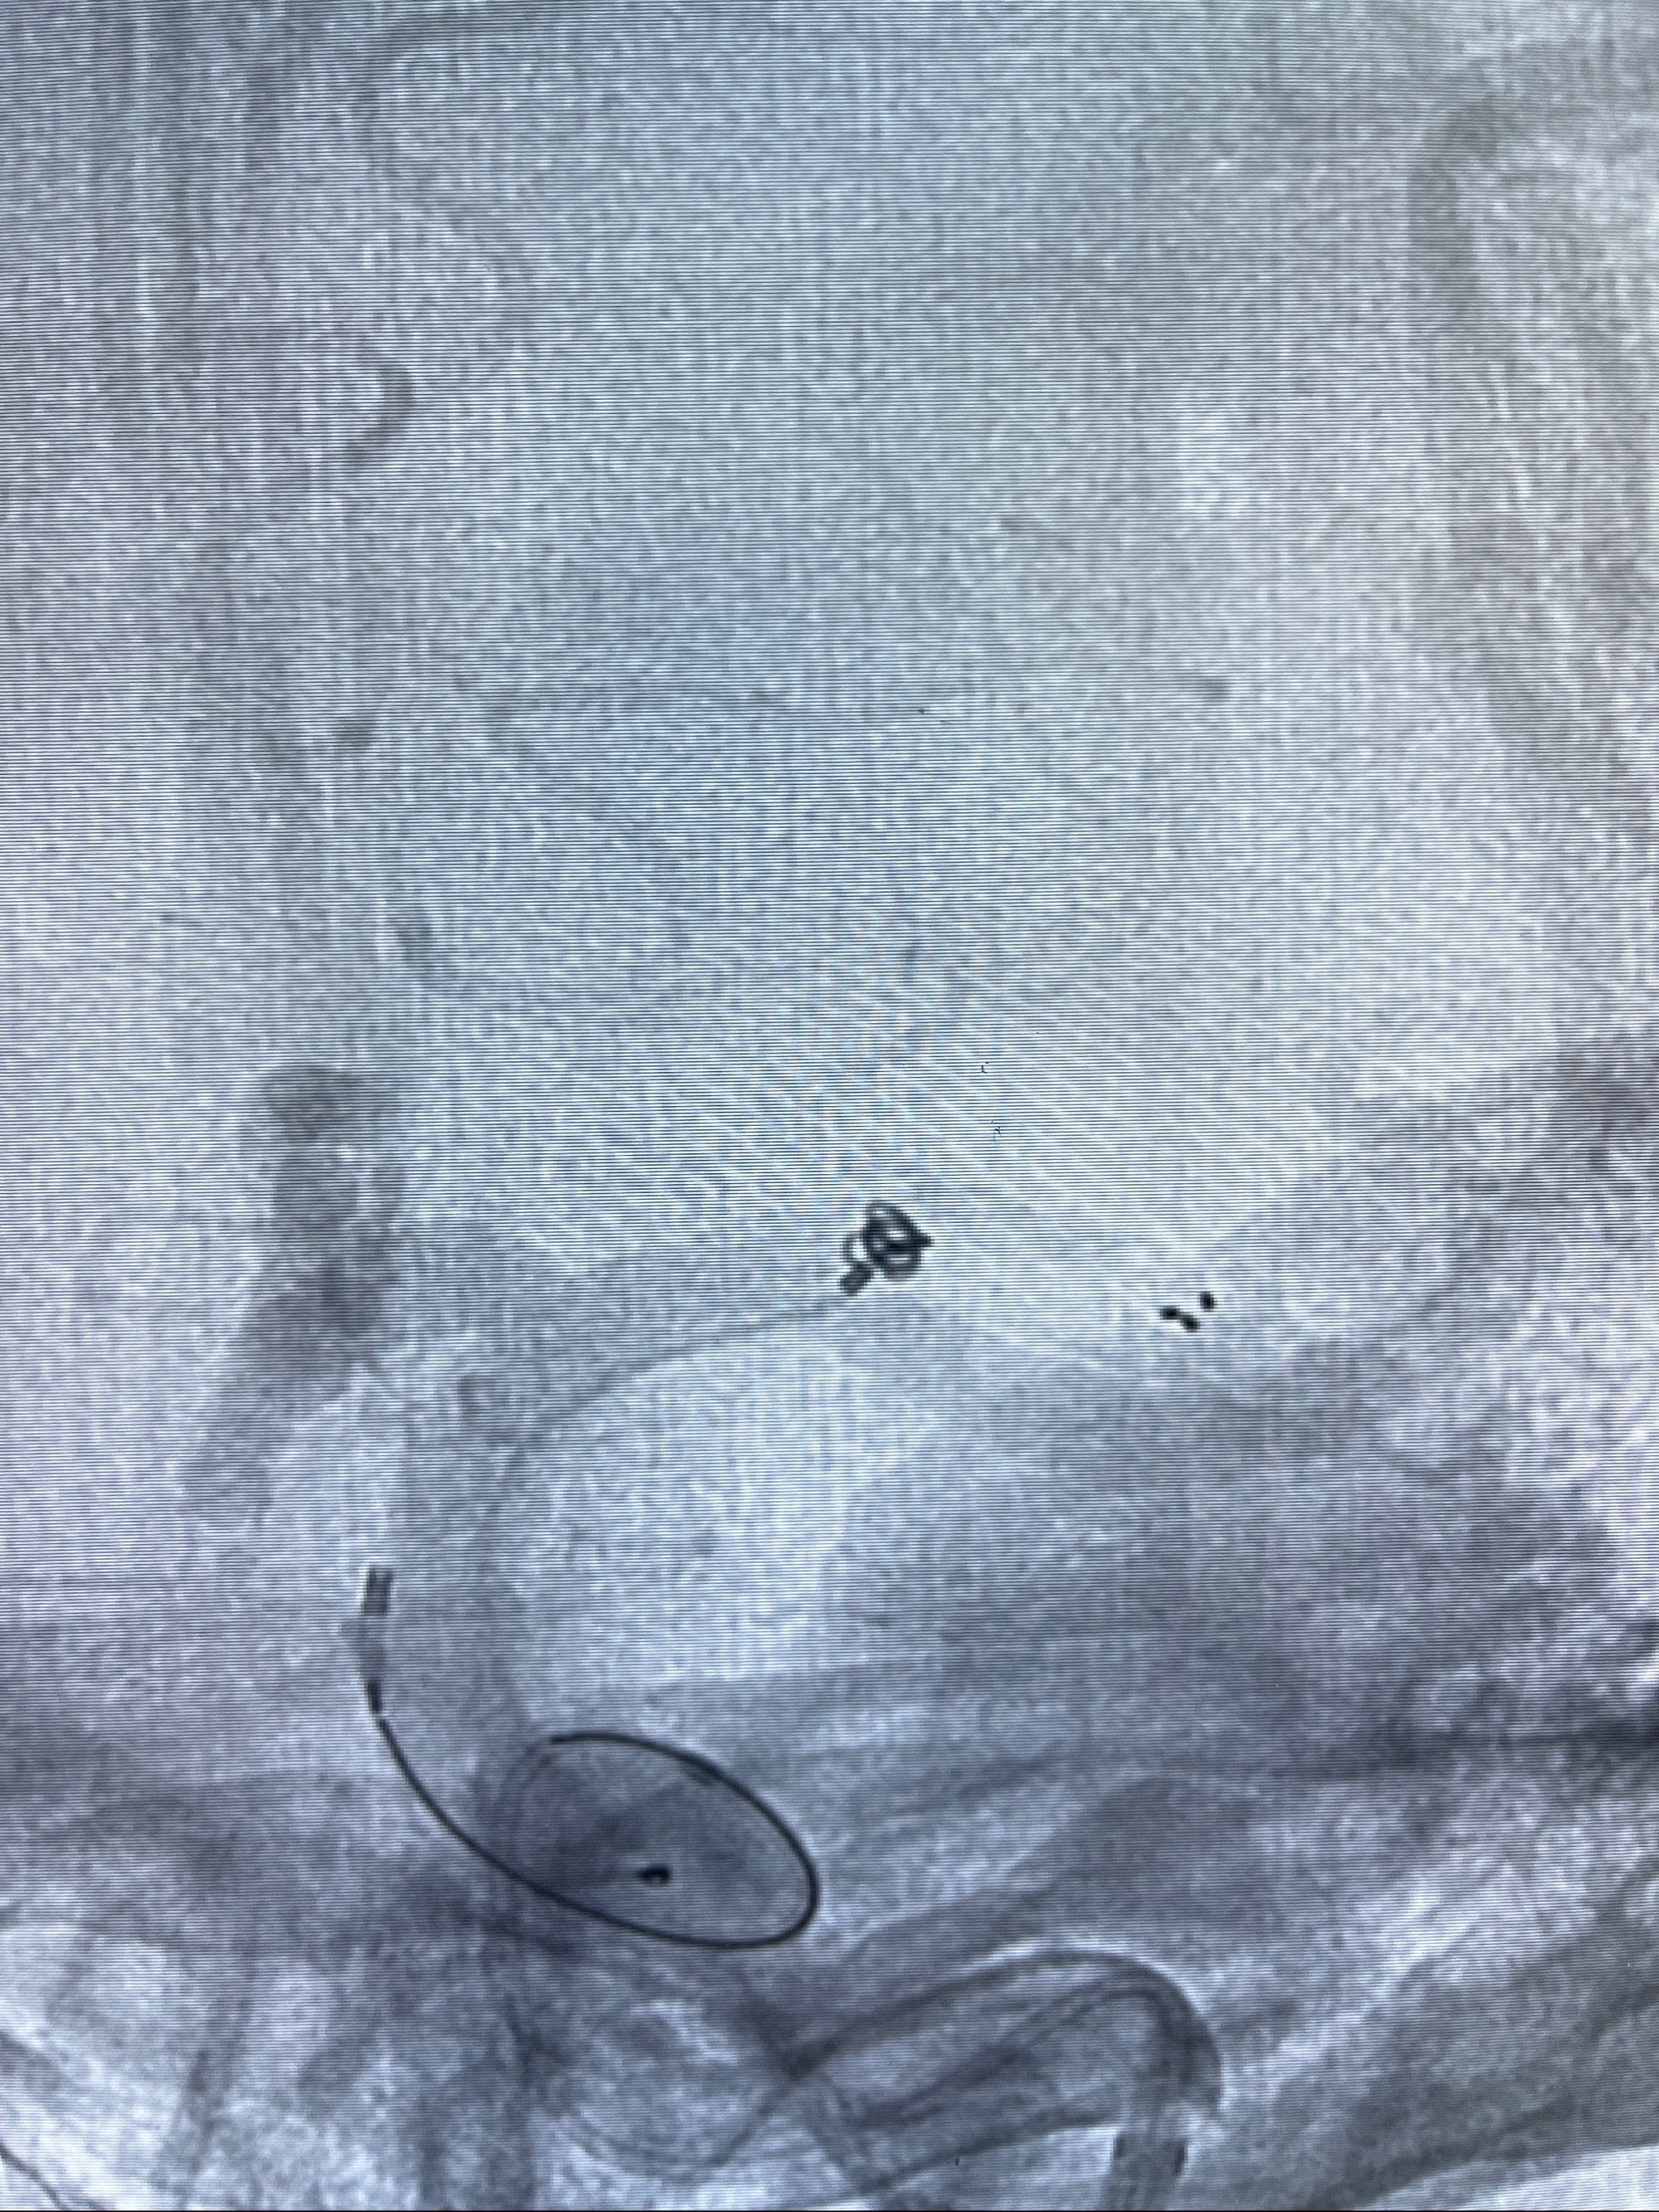

2023-08-14DSA:

左侧大脑中动脉动脉瘤,约2.6-2.8-3.4-2mm大小(瘤颈部、瘤体部、瘤高)

1.左侧大脑中动脉动脉瘤,约2.6-2.8-3.4-2mm大小(瘤颈部、瘤体部、瘤高)

2.外科手术夹闭or介入支架辅助栓塞